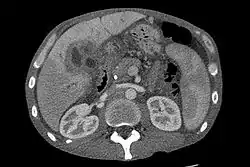

عادةً ما يُستعمل التصوير بالموجات فوق الصوتية للكبد والجهاز الصفراوي كأداةٍ تصويرية أولية في الأشخاص المُحتمل إصابتهم بيرقانٍ انسدادي،[61][62] حيثُ قد يُساعد التصوير بالموجات فوق الصوتية على تحديد الانسداد والتوسع القنوي، كما قد يكون كافيًا في بعض الحالات لتشخيص سرطانة الأقنية الصفراوية.[63] قد يُستعمل التنظير بالموجات فوق الصوتية في إزالة السليلات الصغيرة قبل أن تتحول إلى سرطانة.[64][65] قد يلعبُ التصوير المقطعي المحوسب دورًا مهمًا في تشخيص سرطانة الأقنية الصفراوية،[66][67][68] ولكنهُ قد لا يُظهر بوضوح انتشار السرطانة في الأقنية الصفراوية.[69]